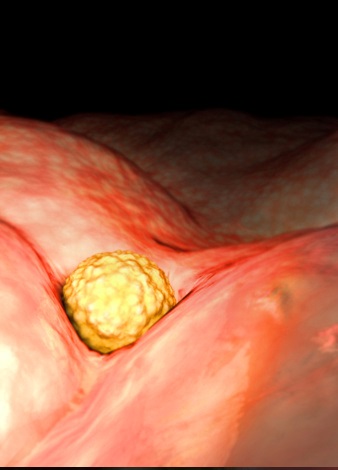

胚胎图

这一时期,你自身可能还没有什么感觉,但在你的身体内却在进行着一场变革。在最初的几周内,胚胎细胞的发育特快,有三层,称为三胚层。三胚层是胎体发育的始基,每一层都将形成身体的不同器官:最里层形成一条原始管道,它以后发育成肺、肝脏、甲状腺、胰腺、泌尿系统和膀胱。中层将变成骨骼、肌肉、心脏、睾丸或卵巢、肾、脾、血管、血细胞和皮肤的真皮。最外层将形成皮肤、汗腺、乳头、乳房、毛发、指甲、牙釉质和眼的晶状体。